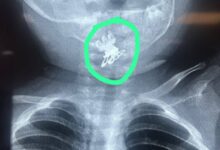

مستشفى الصدر في النجف ينجح بإنقاذ طفلة بعمر سنة ونصف ابتلعت قرّاصة شعر

تمكن فريق طبي بمدينة الصدر الطبية في النجف الأشرف من إنقاذ حياة طفلة تبلغ من العمر سنة ونصف، بعد تعرضها…